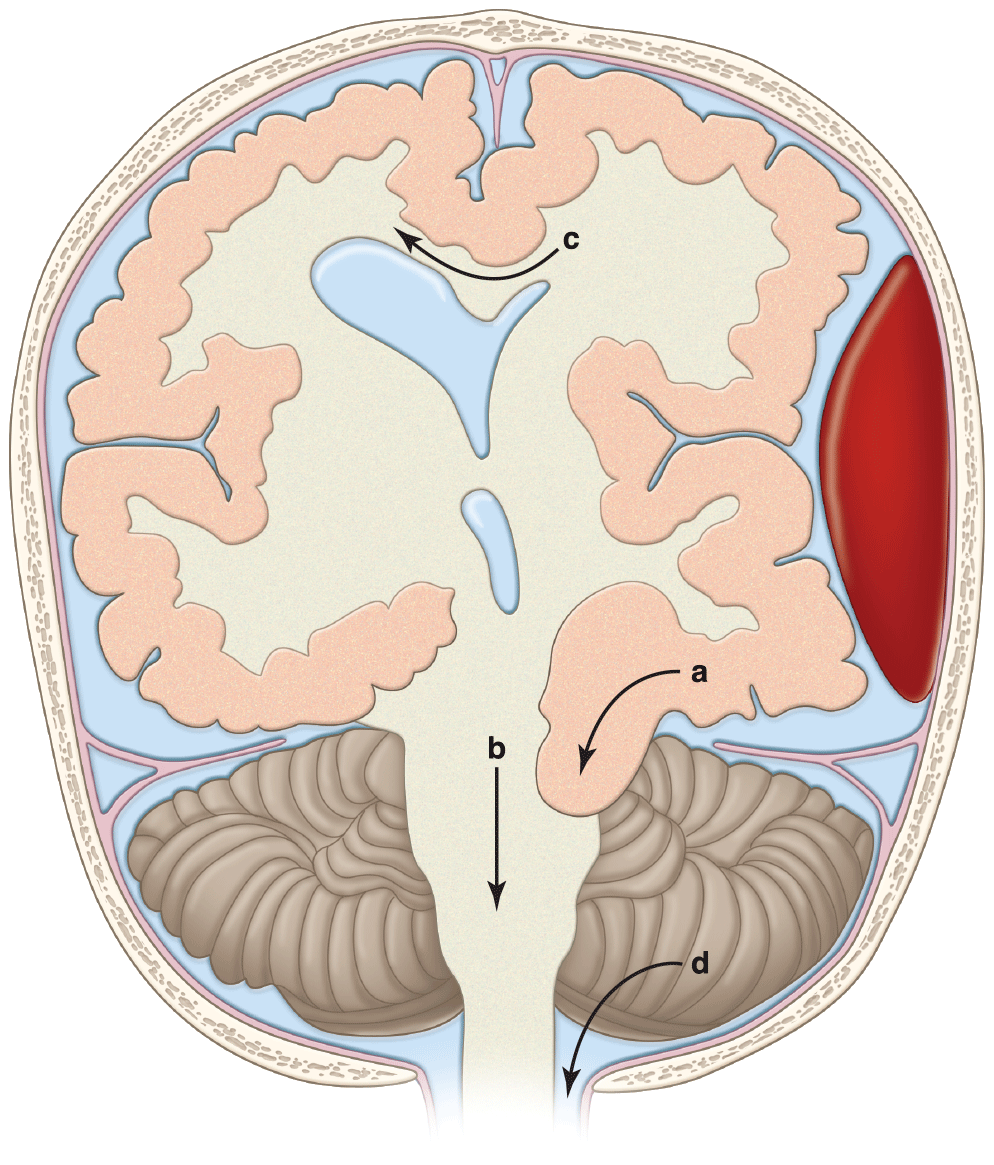

- Subdural hematoma and traumatic subarachnoid blood are the most common hemorrhagic computed tomographic (CT) findings in patients with head injury.